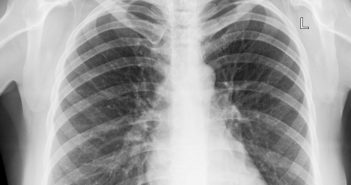

Lungenkrebs ist die häufigste Krebsart in Deutschland. Rund 50.000 Frauen und Männer erkranken jährlich hierzulande…